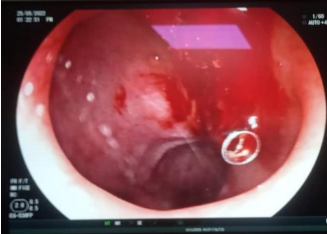

After stabilization his endoscopy was performed which showed a bleeding dieulafoy lesion in the 1st part of the duodenum, clotted blood in the stomach and attenuated blood in the 2nd and 3rd part of duodenum. Hemoclips were applied at the site of lesion and hemostasis secured. (Fig. 2) After hemoclipping his melena stopped and his hemoglobin level was maintained. He was on our follow up in paediatric gastroenterology clinic and his repeat endoscopy after 2 months showed hemoclips in place and no active bleeding. (Fig. 3) His Hemoglobin was 12.5g/dl on follow up and he is thriving well.

Figure 1, 2, 3

Figure 2